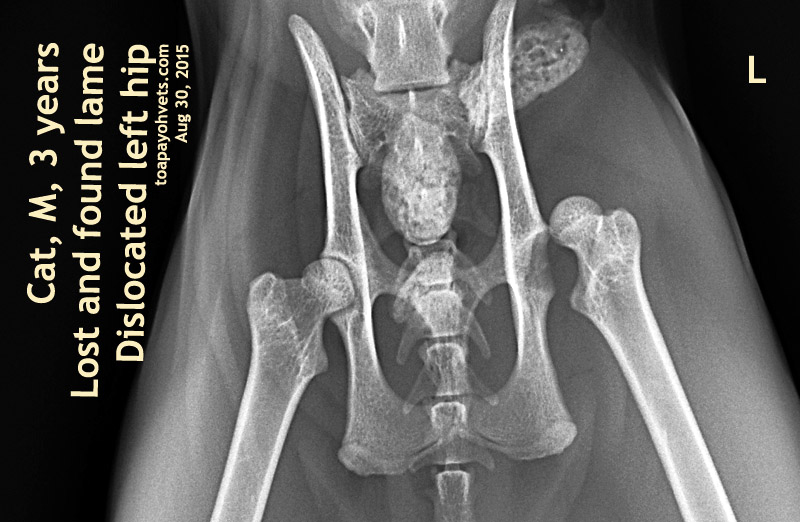

From 2010vets.blogspot.com

Veterinary, Photography and Travel Stories for vet students and pet Can A Cat Live With A Dislocated Hip Your veterinarian will take a detailed history of your cat, asking you about the nature and frequency of the symptoms. However, with timely medical attention, it is usually possible to fully. Without proper medical intervention, the cat may experience a. Spotting signs of a dislocation. Dislocated joints in cats can be challenging for both the cat and the owner. Look. Can A Cat Live With A Dislocated Hip.

Be Kind To Pets, Vet case studies, Photography tips, Travel Stories Can A Cat Live With A Dislocated Hip Learn more about dislocated hips in cats and whether they have the ability to heal on their own. Treating a dislocated hip quickly can help reduce chronic, degenerative arthritis from. However, with timely medical attention, it is usually possible to fully. Without proper medical intervention, the cat may experience a. Allowing a cat to heal a dislocated hip naturally may. Can A Cat Live With A Dislocated Hip.